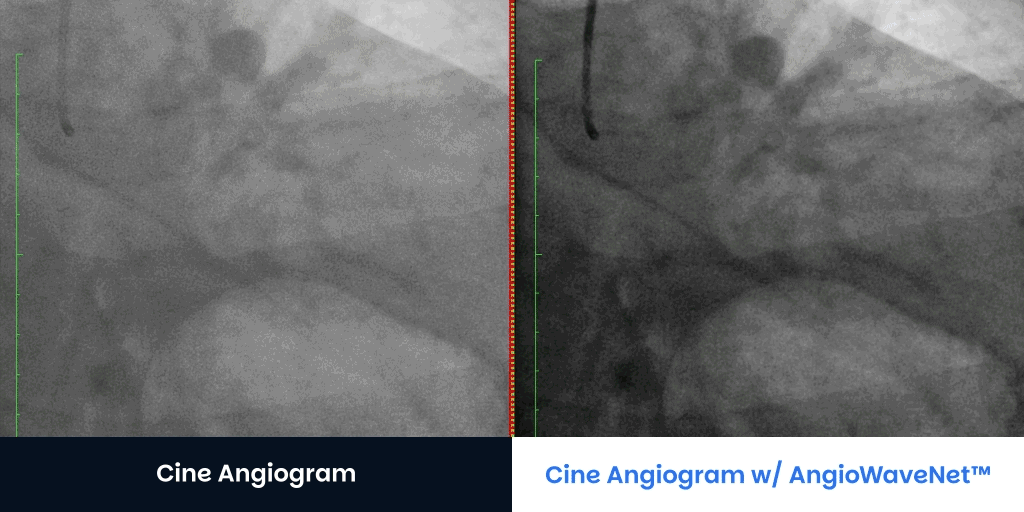

Large Patients BMI > 40 Contact UsGet a Demo CTO Patients Angiograms courtesy of:Jaikirshan Khatri, M.D., Hassan Saleh, M.D. and Weill Cornell Medical Center Left anterior oblique 27°, cranial 1° (unprocessed on left, processed on right) Left anterior oblique 31°, caudal 33° unprocessed on left, processed on right Right anterior oblique 2° caudal 33° (unprocessed on left, processed on right) Right anterior oblique 13°, caudal 36° unprocessed on left, processed on right Contact UsGet a Demo Diagnostic Cine Angiograms Contact UsGet a Demo